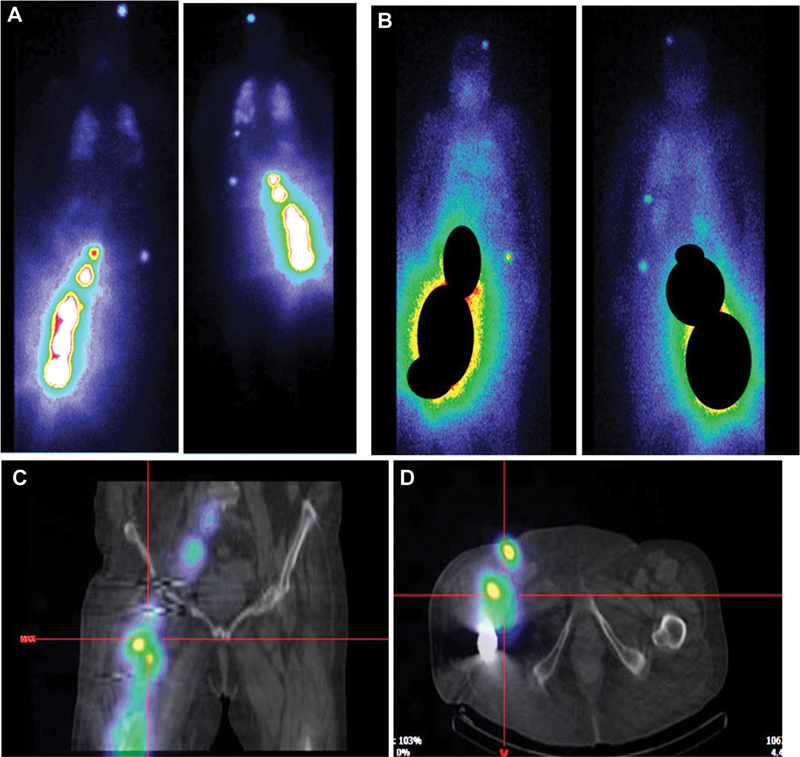

Differentiated thyroid cancer (DTC) is the most common endocrine cancer and its outcome is usually favorable. Its basic treatment is well codified, but its monitoring is much less. The value of thyroglobulin (Tg) is one of the main elements for monitoring DTC, while the use of iodine scintigraphy is becoming less recommended. In this case report, we discuss a clinical situation where a patient presented differentiated thyroid metastatic lesions confirmed by biopsy, uptaking radioactive iodine, with undetectable levels of Tg (in the absence of autoantibodies). We discuss the various hypotheses explaining this clinical situation, the potential advantages of performing periodic iodine scintigraphy in some intermediate and high-risk patients and report the documented clinical benefit of radioiodine therapy.